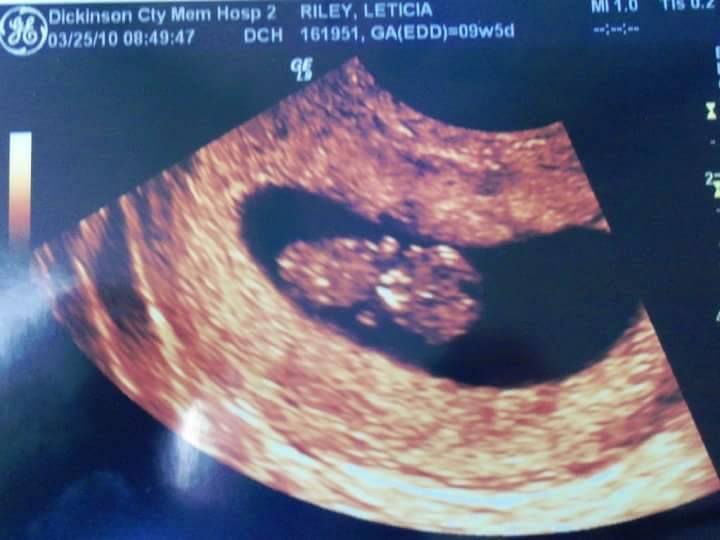

At their first OB appointment in Leticia’s eleventh week of pregnancy, Leticia and Jeremy were excited to hear their child’s heartbeat from within her womb. The doctor searched with the Doppler tool, but could not locate the heartbeat. He moved them to the ultrasound room down the hallway and began the visual examination.

“I couldn’t understand what we were seeing on the fuzzy screen,” Leticia said, “but the doctor broke the deafening silence by telling us that the first thing he noticed was that there were two gestational sacs. I was pregnant with twins. He then went on to explain that, according to the ultrasound picture, it appeared to be a six-week pregnancy, not an eleven-week pregnancy.”

“My heart sank,” she said. “I immediately went to have an ultrasound and testing done to ensure the safety of our baby. There I witnessed the most beautiful vision my eyes have seen–our baby squirming around, looking like a little Teddy Graham with only buds for arms and legs. I was in love!”